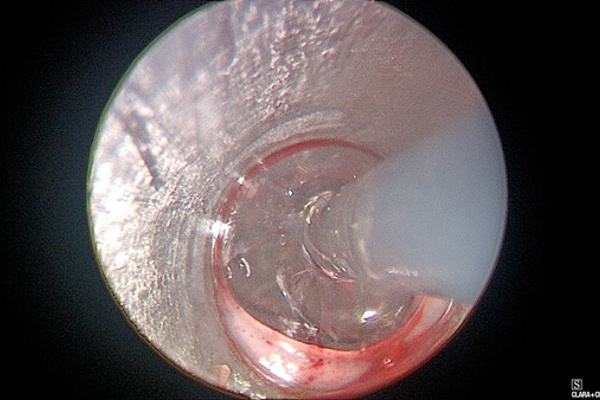

Transnasal oesophagoscopy (TNO) and balloon dilatation under a local anaesthesia